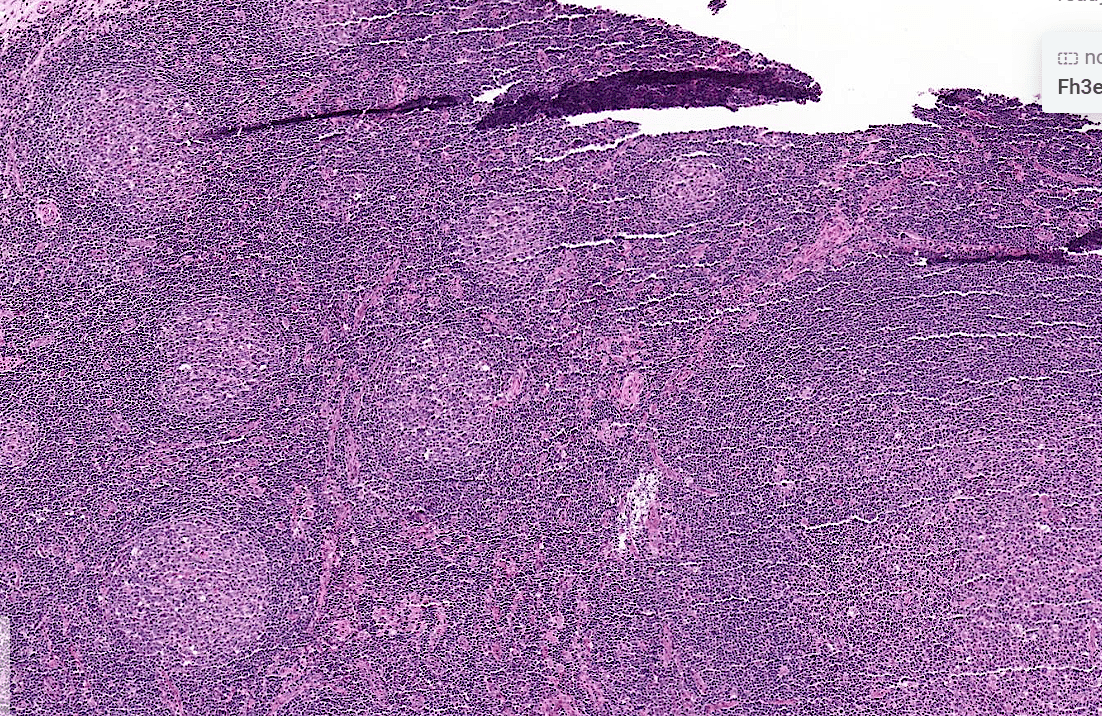

Pathology Lab 1

不太考

應該會考